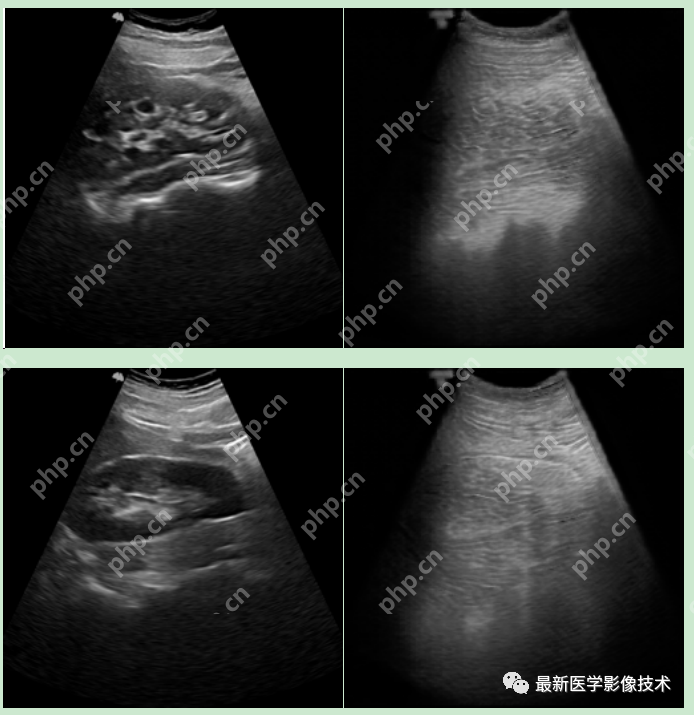

5、验证集部分生成结果

左图为低质量图像,中间为生成的高质量图像,右图为真实的高质量图像。